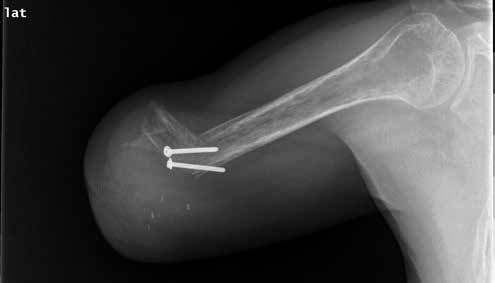

1974 entwickelten Marquardt und Neff die Winkelosteotomie für transhumeral amputierte Patienten 30. Das Ziel der Winkelosteotomie war einerseits, das Längenwachstum des Knochens und somit die Gefahr der Hautperforation bei Kindern und Jugendlichen zu reduzieren, andererseits eine möglichst rotationsstabile und zugfeste Stumpf-Prothesen-Anbindung zu ermöglichen 31. Bei der Winkelosteotomie nach Marquardt wird aus der Humerus-Diaphyse fünf bis sieben Zentimeter proximal des knöchernen Stumpfendes ein Keil mit einem Winkel von 70 bis 90 Grad entfernt, um das distale Humerus-Fragment annähernd rechtwinklig zum proximalen Humerus durch eine Knochenschraube oder einen Kirschner-Draht zu fixieren 32 (Abb. 2). Dadurch entsteht ein konturiertes Stumpfende mit der Möglichkeit, mittels spezieller Schafttechniken eine stabile Anbindung der Prothese ohne Schultergurte zu schaffen. Durch diese Methode kommt es allerdings unweigerlich zu einer Verkürzung der Stumpflänge. Die Winkelosteotomie sollte deshalb nur bei langen transhumeralen Stümpfen zur Anwendung kommen. Nachuntersuchungen haben allerdings eine Geradstellung des Knochenfragments bereits in den ersten 24 Monaten vor allem bei Patienten unter 16 Jahren gezeigt 33.